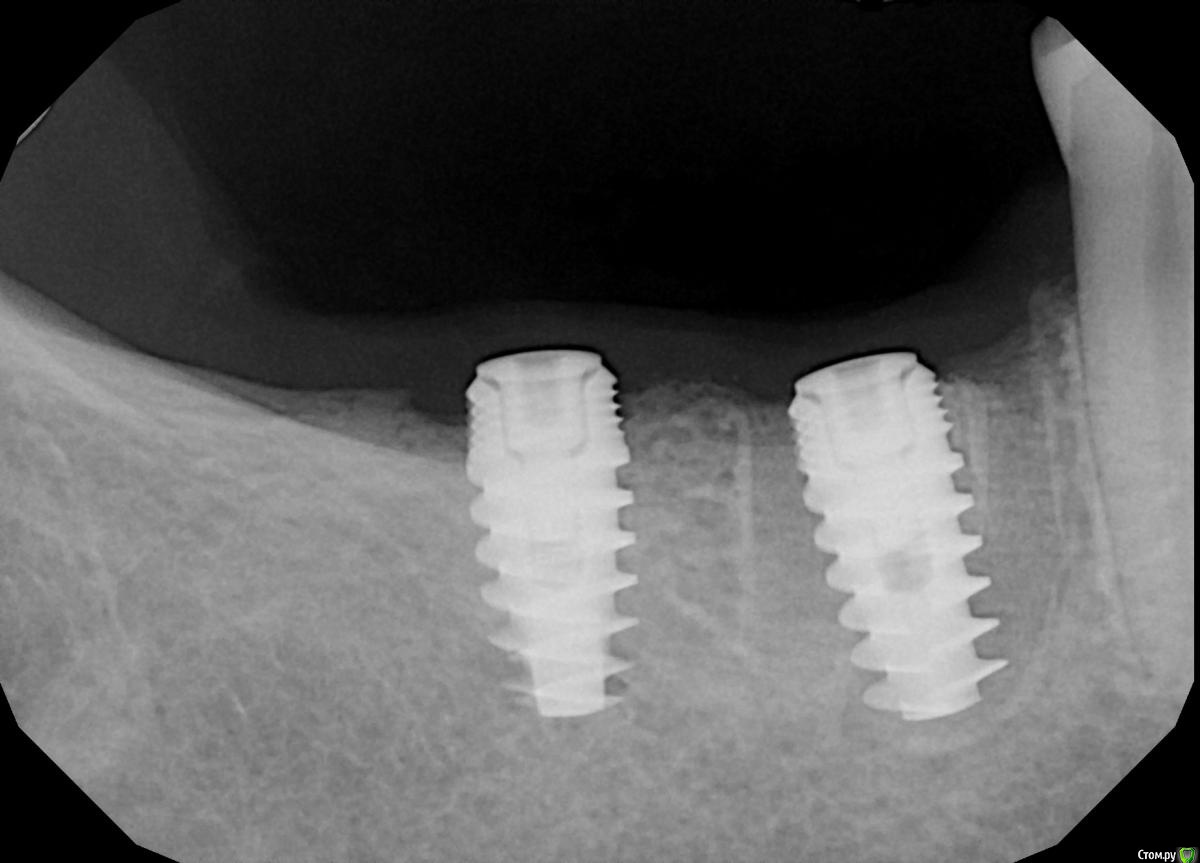

Demerchyan26 Опубликовано 3 марта, 2016 Поделиться Опубликовано 3 марта, 2016 Решил показать свой небольшой эксперемент. Ничего необычного, сложное удаление 1 час + имплантация, только без графта, лишь сгусток и торк меньше 5, не мог заглушку прикрутить. Открывал через 3,5 - 4 месяца. Система бюджетная - SGS, 7-ку немного не докрутил))) Ссылка на комментарий

Demerchyan26 Опубликовано 3 марта, 2016 Автор Поделиться Опубликовано 3 марта, 2016 Возможно, но это не первая моя операция без графта, но первая, когда перегородки почти не осталось и торк получился минимальный, имплант слишком широкий взял. Ссылка на комментарий

red_butler Опубликовано 3 марта, 2016 Поделиться Опубликовано 3 марта, 2016 Возможно, но это не первая моя операция без графта, но первая, когда перегородки почти не осталось и торк получился минимальный, имплант слишком широкий взял.Проблема не в ширине, нужен был более длинный винт. А вот то что дистальный не досадили, это косяк, кость еще уйдет. Что с мягкими тканями? Ссылка на комментарий